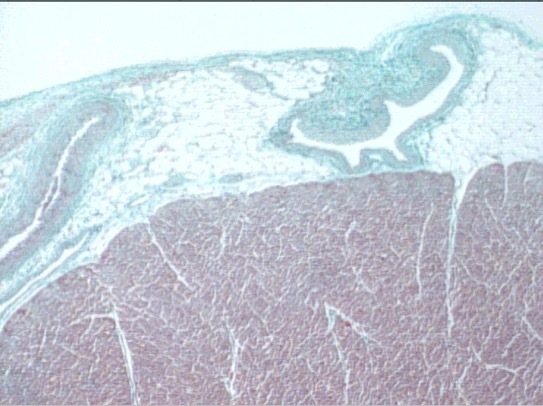

inner heart

myocardium

endocardium

endothelium

subendothelium (type I collagen)

subendocardium (purkinje fibers and CT)

epicardium

connecitive and adipose tissue

(mesothelium)

vein

capillaries

intercalated disc